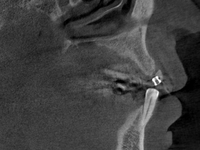

Bei nicht oder nicht vollständig durchgebrochenen Weisheitszähnen wird die darüber liegende Schleimhaut beiseite geschoben und der darüber liegende Knochen entfernt. Dann wird der Zahn mit einem Hebel entfernt. Ist dies aus anatomischen Gründen nicht im Ganzen möglich, wird das Durchtrennen des Zahnes notwendig. Das Trennen des Zahns ist obligat wenn die Platzverhältnisse keine andere Entfernungsmethode zulassen oder sich die Zahnwurzeln in unmittelbarer Nervnähe befinden. Die Wunde kann vernäht oder offen gelassen werden. Um Folgeschäden wie eine Taubheit der Unterlippe zu vermeiden kann präoperativ ein 3D DVT ( DIGITALES VOLUMENTOMOGRAMM ) zur Abklärung der Lagebeziehung von Wurzeln und Nerv sowie zur OP-Planung angefertigt werden.

Zu einer Wurzelspitzen-Entfernung wird Ihr Zahnarzt oder Kieferchirurg dann raten, wenn ein chronisch entzündlicher Prozess durch eine Wurzelbehandlung nicht behoben werden kann oder eine konventionelle Wurzelbehandlung nicht möglich ist. Auch wenn sich im Röntgenbild Veränderungen im Bereich der Wurzelspitze zeigen, die nicht eindeutig zuzuordnen sind, kann eine Wurzelspitzen-Resektion empfehlenswert sein. Um die Region der Wurzelspitzen genauer abzubilden ist es präoperativ möglich, durch ein 3D DVT (DIGITALES VOLUMENTOMOGRAMM) die Region dreidimensional abzubilden, um so eine bessere OP-Planung zu erhalten oder sich über die Frage der Erhaltungswürdigkeit des Zahns klar zu werden.